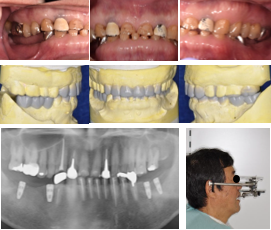

こうした基本的な手技の習得と、考える力の修練を両輪で実施することが重要であり、その土台をきちんと築いていくことで難症例にも対応できるようになると考えています。ここに示すのは過去の研修医や修練歯科医の先生が担当した症例の一部です。難しい症例やアドバンス的な治療にも指導医とのディスカッションやチェックを何度も繰り返しながら治療を担当してもらいました。